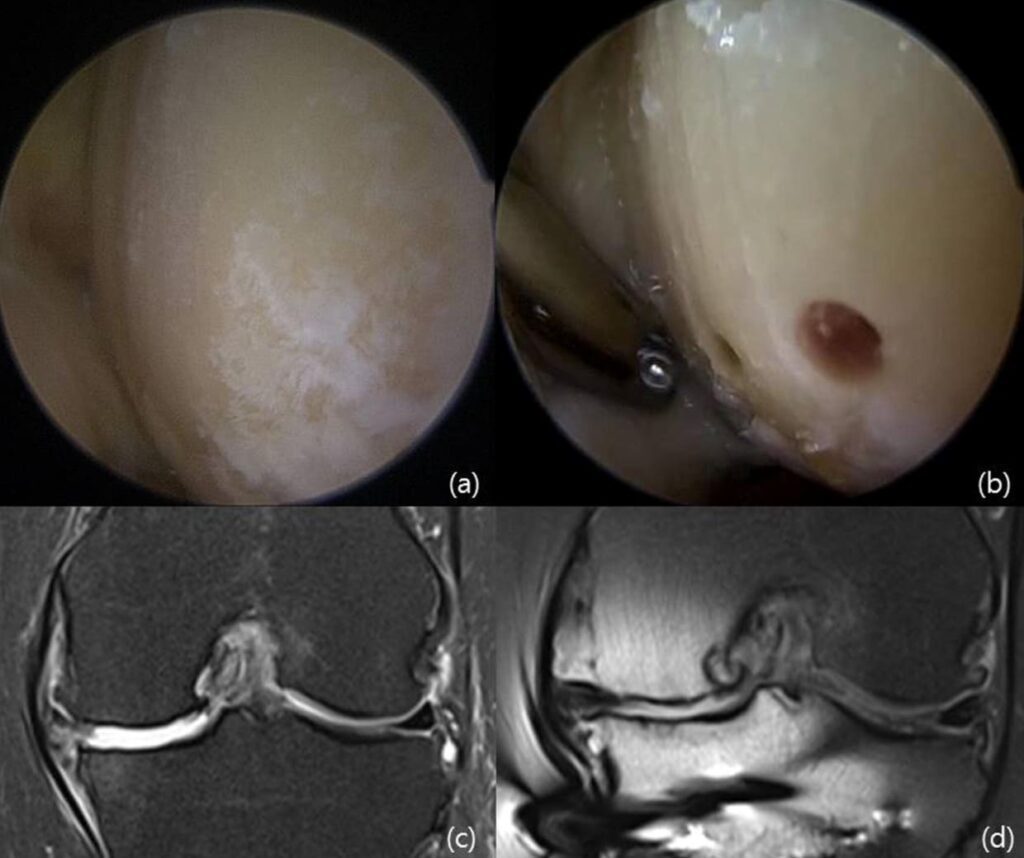

Arthroscopic comparison of knee cartilage before treatment and during follow-up after high tibial osteotomy combined with implantation of umbilical cord blood-derived mesenchymal stem cells. This indicates that the treatment helped the damaged cartilage areas begin to fill in with new tissue, which may contribute to improving joint function.

doi.10.4252/wjsc.v12.i6.514